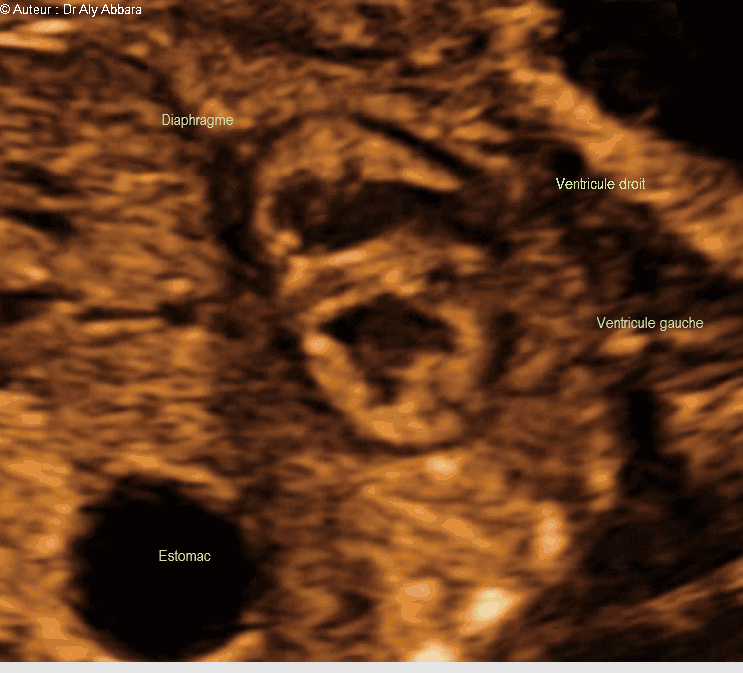

Cœur foetal - la coupe standardisée des trois passant dans la pointe cardiaque : foetus de 22 SA

Images échographiques montrant l'aspect normal de la coupe cardiaque passant par la pointe du cœur et qui comporte de haut en bas sur cette image :

* La partie fundique du ventricule droit contenant la plaque modératrice de la valve tricuspide.

* Le septum interventriculaire qui en continuité avec les parois du ventricule gauche.

*La partie fundique du ventricule gauche contenant les deux piliers de la valve mitrale.

On peut identifier également sur cette image le diaphragme séparant l'estomac de la cavité de la cage thoracique.

Foetus de 22 SA et 3 jours.